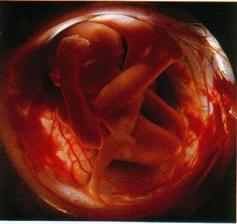

zázrak lidské života na videu